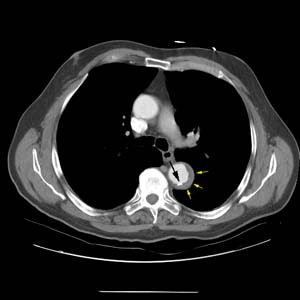

More inferiorly, there is displacement of an intimal calcification (black arrow) by the high density intramural hematoma (yellow arrows).